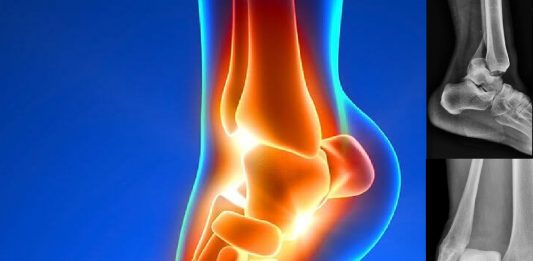

Ayak Bileği Çıkıklarına Genel Yaklaşım

Ayak bileği çıkığı neredeyse her zaman kemik kırıkları ile birlikte meydana gelir. Ayak bileği çıkıklarının yüzde 25’i açık yaralanmalardır. Ayak bileği kırıklı çıkıkları, ayak bileği kırıklarına göre çok daha fazla majör komplikasyona neden olduğu için önemli yaralanmalardır ve acilen tedavi almaları gerekmektedir. Çıkıkların redüksiyonunda yaşanan gecikmeler talar kubbenin osteokondral yaralanmasına ve ayak bileği hareketinin ileri … Ayak Bileği Çıkıklarına Genel Yaklaşım okumayı sürdür